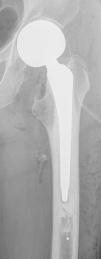

The constancy of the postero-internal location and at a distance that could correspond to the anatomical position of this femoral nutrient bundle should lead us to consider extrusion of the cement towards the veins or arteries that make up the bundle (Fig. 2). Likewise, the linear morphology of the radiographic image suggesting the vessel being occupied by cement, venous valves being observed, differs completely from that produced by a cortical defect or a periprosthetic fracture (Fig. 3), which would result in an irregular image without tubular appearance or the presence of valves.13